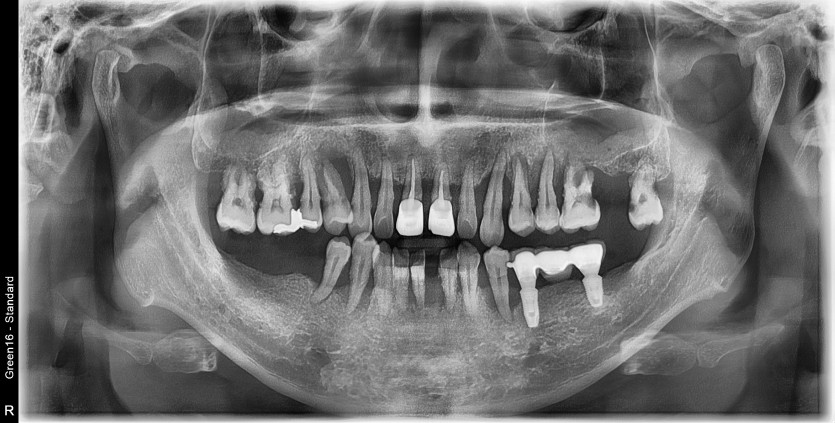

전체 임플란트 증례입니다.

16개의 임플란트로 완성하였습니다.